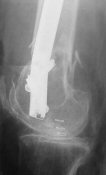

THX, initial images are

1,

2.

At that moment we had in stock only the 10 mm solid nails so of course there was no idea about early weight bearing. But it was quite enough for early knee ROM excersises (see attached). Two locking screws through the distal block provided that.

A new toy is more interesting and fashionable. And anyway it is not panacea, i have already seen presentations with LISS failures like the attached one presented by D.Seligson. And people also demonstrated incisions say that the method is not so LESS invasive as it supposed to be.